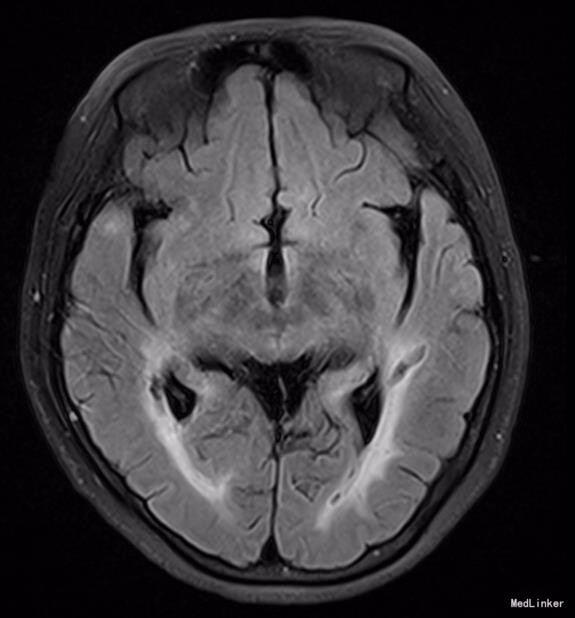

神清,说话吐词清晰。双侧瞳孔等大等圆,眼球运动正常,光反射灵敏,无面舌瘫,颈软。左手握力下降,右下肢轻瘫试验阳性,双上肢腱反射稍高,双侧膝反射亢进,霍夫曼征及内罗里索征阳性。直线行走试验阳性,闭目难立征阴性,双侧指鼻试验阴性。双侧病理征未引出,四肢浅感觉等称。实验室检查未见明显异常。MRI示:脑干、双侧颞极、外囊、额顶叶、放射冠区及丘脑、脑桥异常信号,结合MRS提示符合缺血性改变,部分软化灶形成.结合病变位置(颞极、外囊)及患者年龄,考虑CADASIL可能。头颈血管大致正常,NOTCH3基因见图